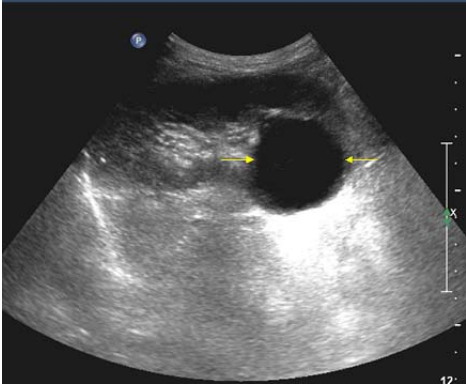

70.附圖為一體檢病人超音波檢查之右腎長軸切面圖,箭號所示最可能為何?

(A)惡性腫瘤 (B)腎囊腫 (C)腎產氣性膿瘍 (D)腎水腫